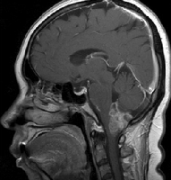

腦干腫瘤在成年患者中并不常見(jiàn)。出現(xiàn)的平均年齡是生命的四個(gè)十年,總生存期約為54-64個(gè)月。它們?cè)诹餍胁W(xué)數(shù)據(jù)中占全部腦腫瘤的小于2%。那些僅位于延...

延髓膠質(zhì)瘤是絕癥嗎?腦干腫瘤在成人患者中很少見(jiàn)。出現(xiàn)的中位年齡為生命的四個(gè)十年,總生存期約為54-64個(gè)月。它們占流行病學(xué)數(shù)據(jù)中全部腦腫瘤的2...